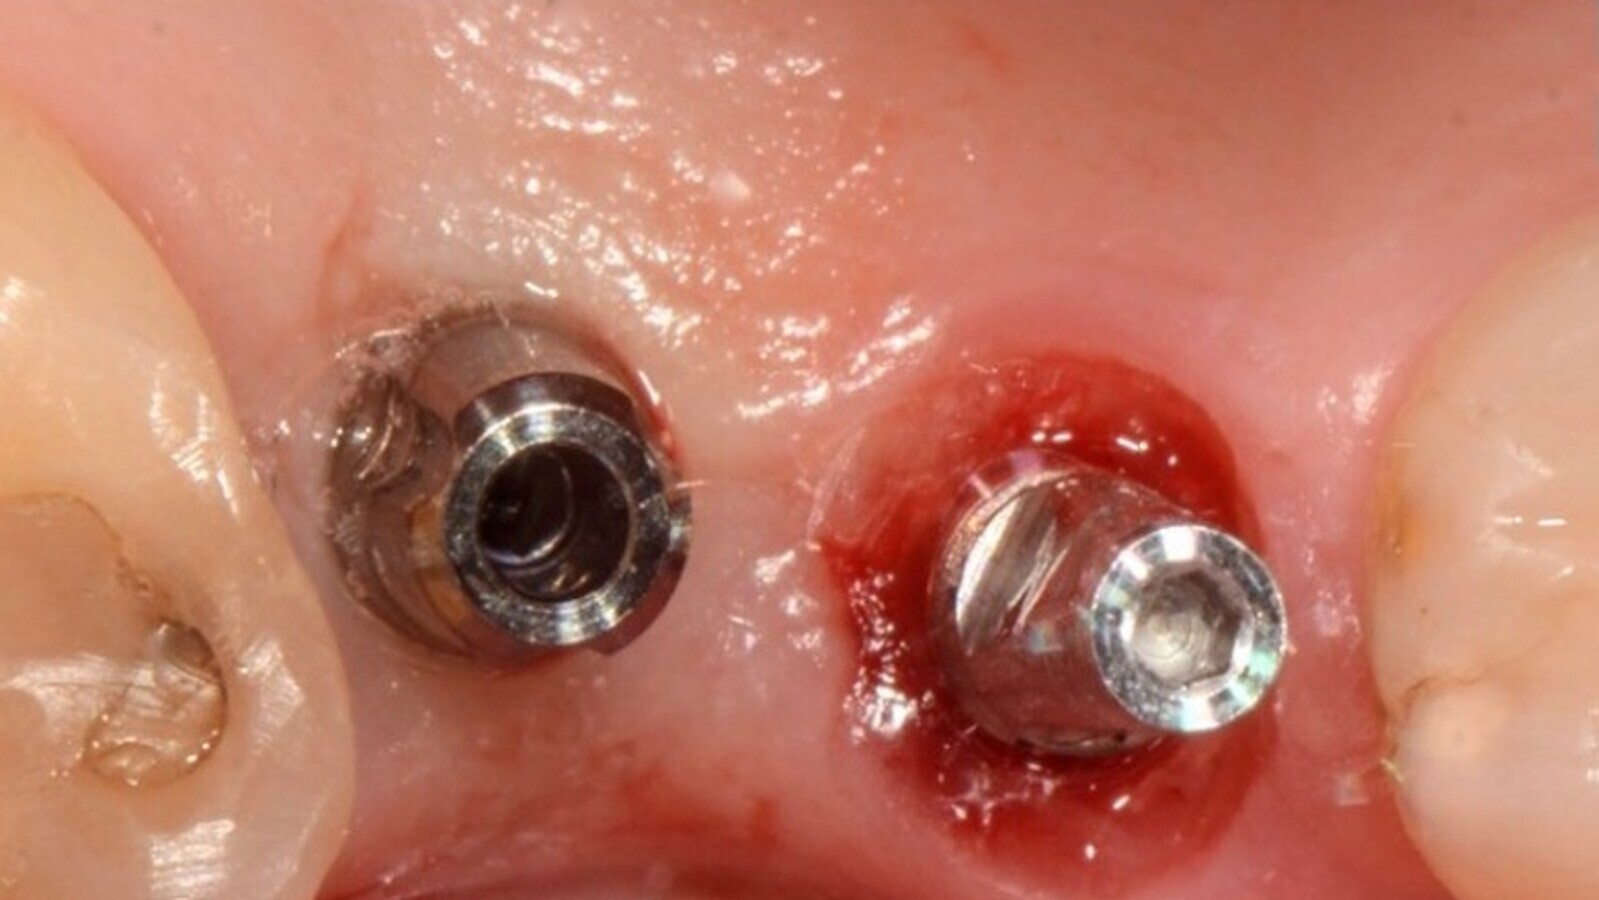

Aplicación del aditamento Sculgar

En principio, se utiliza para preservar el tejido gingival y engañar de alguna manera al cuerpo humano ante la pérdida de la pieza dentaria y la consecuente cicatrización fibrosa de la mucosa gingival5. No utilizamos tapones cicatrizales, ya que a veces resultan compresivos del tejido blando.

Fig. 6. Comparación entre un implante con tapa cicatrizal y otro con Sculgar (Imagen gentileza de NTI).

Fig. 7. Sculgar posicionados inmediatamente tras la cirugía.